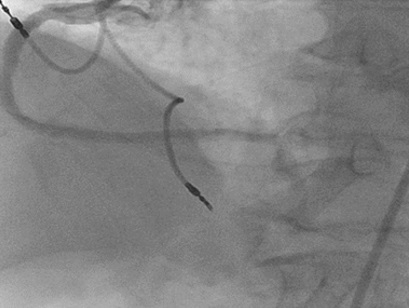

A 60-year-old presents with RCA ISR.  He is status post CABG in 1997 with both SVG to RCA and circumflex occluded and a patent left internal mammary to the LAD.  On 9/14, he underwent PTCA for 2 stent ISR lesions.  During previous intervention, it was noted that there was difficulty with guide support and a very stiff Amplatz guide needed to be used to pass the balloon catheters across the lesions.  He now presents with angina with minimal activity and an outside angiogram revealed recurrent ISR and an EF of 40%.  An 8 French JR4 guide was used and the CrossLock™ was inserted over an .014 Whisper wire and FineCross.  The inflation of the CrossLock™ aided the passing of the wire, FineCross and subsequent .9mm Laser over the lesions.  Following this, a 3.5mm x 8mm Alpine stent was placed at the distal ISR site and a 3.5mm x 12mm placed at the proximal lesion.  The vessel was widely patent following treatment.

Figure 6. A JR4 8 French guide is at the origin of the right coronary artery. Angiography shows two focal instent restenotic lesions.

Figure 7. The CrossLock™ is in place at the origin of the vessel allowing placement of the .9mm Laser (not shown).